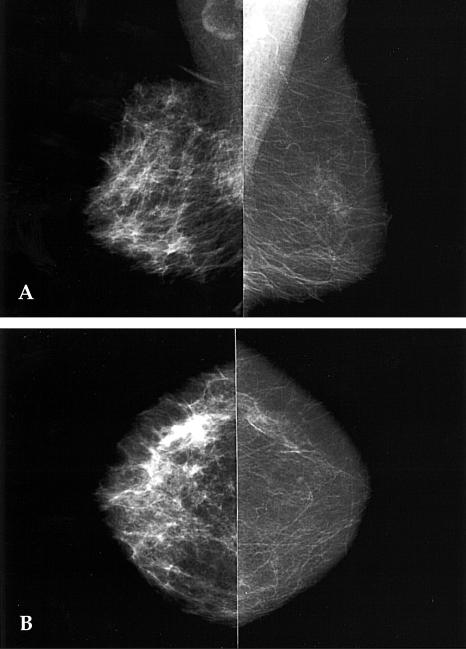

Breast edema is defined as a mammographic pattern of skin thickening, increased parenchymal density, and interstitial marking. It can be caused by benign or malignant diseases, as a result of a tumor in the dermal lymphatics of the breast, lymphatic congestion caused by breast, lymphatic drainage obstruction, or by congestive heart failure. Here we describe several conditions, that cause unilateral breast edema with the aim of familiarizing radiologists with these disease entities.